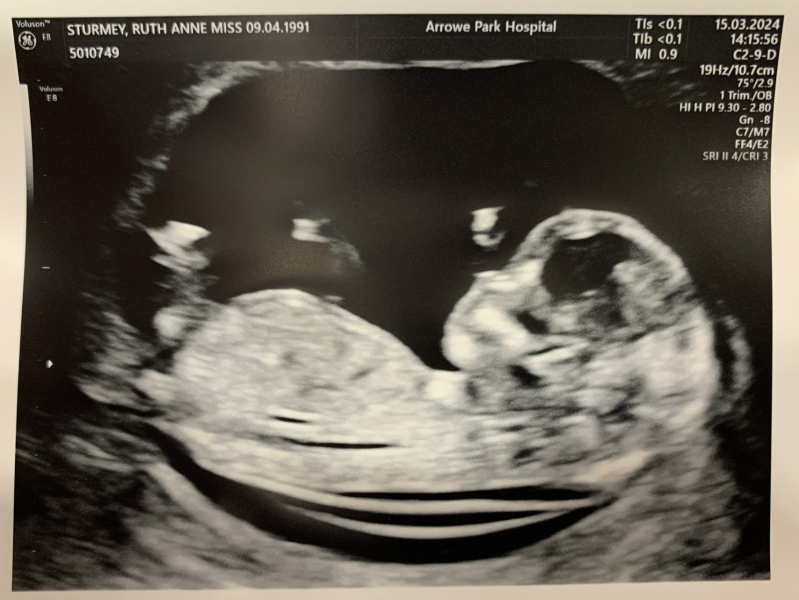

Cat2022 · 15/03/2024 10:21

Lovely scans everyone!

There's officially a baby in there! All looking good and due date moved forward by one day. We walked out of the hospital after the scan and there was a huge rainbow too which felt a bit magical!

Can't wait to tell our DD tonight and then rest of family.

If anyone wants to guess based on the nub (what even is a nub?) then please feel free 😁

Good luck to everyone else having their scans today, I know there's a few of us x

I feel I can now relax! After a week of ordered rest due to old blood spotting and cramps and all my pregnancy symptoms going. our scan went well!

No concerns from consultant, seems happy with everything.

Due date 23rd September 🥰

I was further along today! Chuffed 😅 13+2

due the same day as my nans birthday and I wanted to name the baby after her if it’s a girl!

But I have no idea how to guess gender I am not bothered either way! Just so so happy it’s done and went well!!

I survived the long morning wait! Baby took 10 minutes to stop standing on its head but behaved in the end and all looking good. So relieved!

I had mine and everything went well, the sonographer said the baby was laid in a great position so was snapping away to get some nice pics for us! They managed to get my bloods first attempt too and going by my last scan baby should've been measuring 12+2 or 12+3 but was measuring 12+6 today (some measurements were 13 and 13+1 but the sonographer used the lowest one) so very happy all around! Puts my due date at 21st September